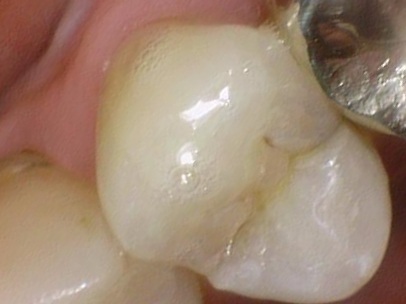

실제 케이스 1

딱딱한 과자를 먹었는데 그 후로 누르거나 씹을 때 통증이 있다고 오신 환자분입니다.

치아에 금이 간 것이 보이고 핀셋으로 만져보면 벌어집니다.